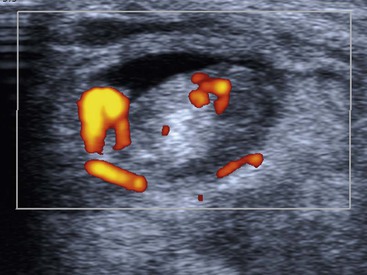

The posteromedial ankle tendons comprise the tibialis posterior (TP), flexor digitorum longus (FDL) and flexor hallucis longus (FHL) tendons. TP is the strongest of these, with approximately twice the cross-sectional area of FDL. It is also the most frequently affected by pathology. TP function is important in maintaining the medial arch of the foot (with the spring ligament) and tears of TP may lead to flat foot deformity. An os naviculare is a sesamoid bone located at the insertion of TP. Tenosynovitis appears as increased fluid in the tendon sheath, sometimes with altered appearance of the tendon itself. Ultrasound can help confirm the diagnosis by demonstrating hyperaemia on Doppler interrogation of the tendon or its sheath (Fig. 46-55). On MRI, a greater cross-sectional area of fluid than tendon is suggestive of tenosynovitis. The FHL and very occasionally the FDL tendon sheaths communicate with the ankle joint in a minority of individuals. Therefore fluid in these tendon sheaths may relate to an ankle joint effusion.